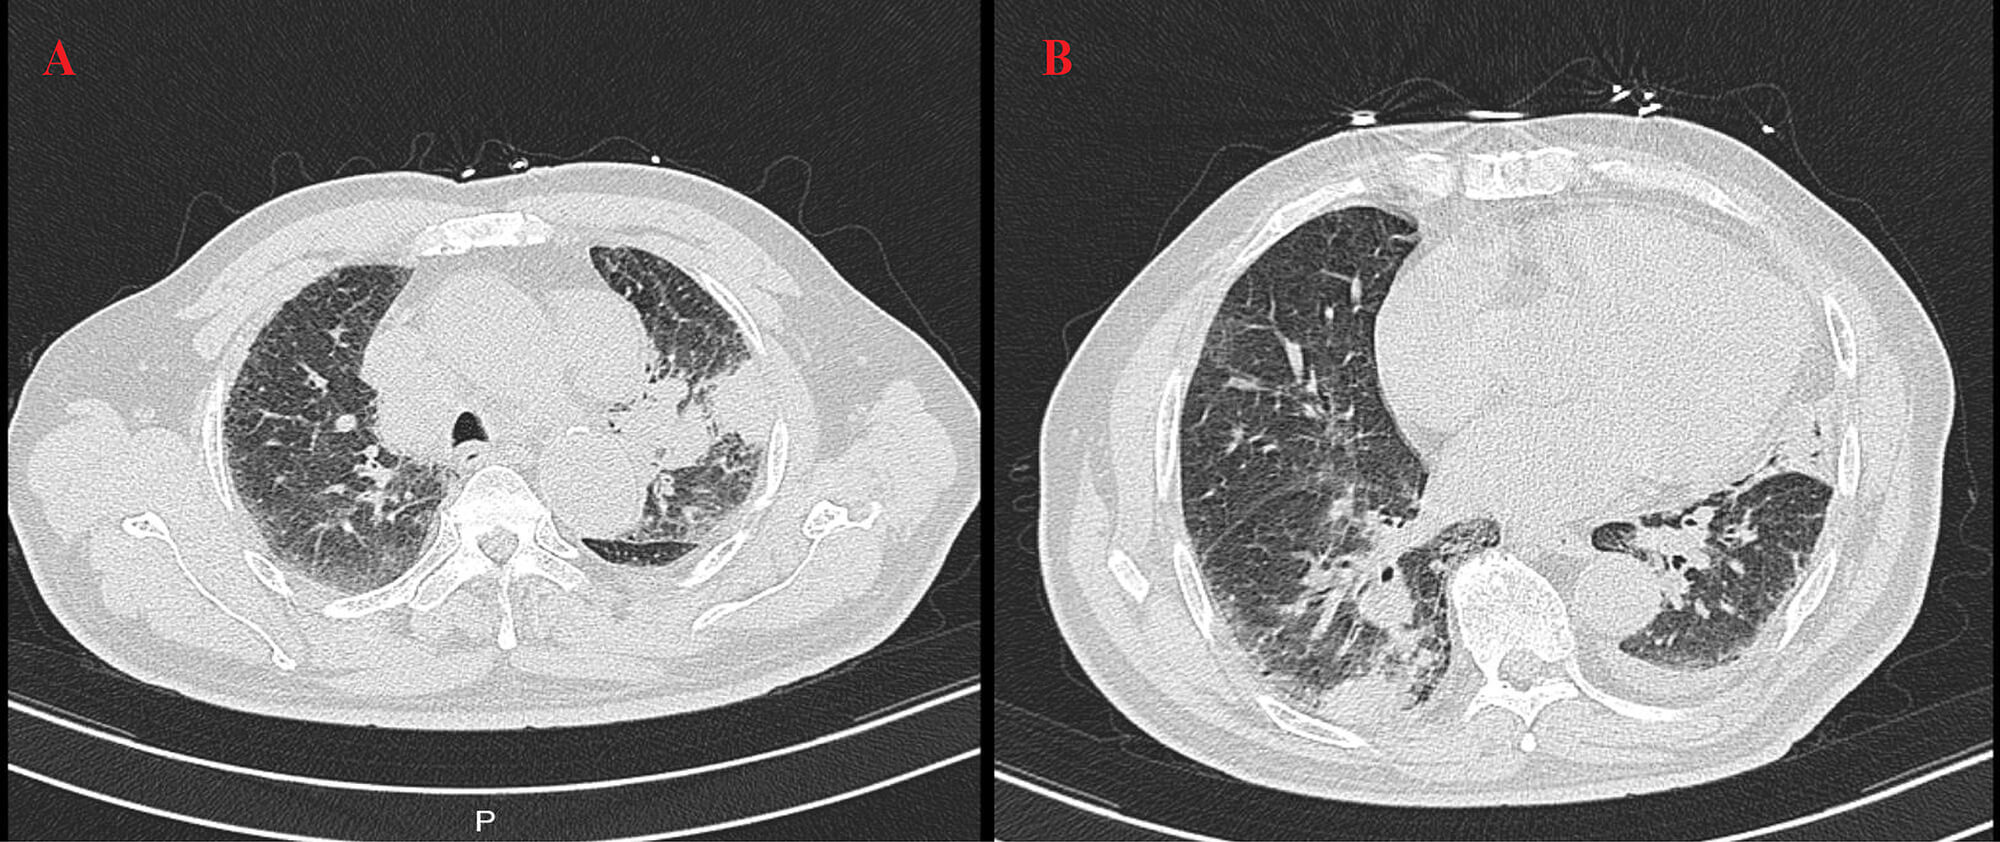

In July 2024, the patient presented to the Department of Neurology at the Second Affiliated Hospital, Zhejiang University School of Medicine with limb weakness but did not receive specific treatment at that time. A high-resolution computed tomography (HRCT) scan of the chest without contrast (Fig. 1) revealed a mass lesion in the left upper lobe and patchy consolidation in the right lower lobe. Bronchoscopic biopsy showed atypical naked nuclei in the mediastinal 4R lymph node and the anterior segment of the right upper lobe, consistent with small cell carcinoma. Immunohistochemistry (IHC) demonstrated positivity for pan-cytokeratin (CK-PAN), thyroid transcription factor-1 (TTF-1), synaptophysin, chromogranin A, cluster of differentiation (CD) 56, and insulinoma-associated protein 1 (INSM1), with a Kiel-67 (Ki-67) index of approximately 60%, confirming the diagnosis of SCLC (Fig. 2) [12]. Cytological examination of the 4R lymph node also revealed small cell carcinoma cells. Electromyography performed on 5 August 2024, demonstrated a low-frequency decrement and high-frequency increment across multiple muscles; reduced amplitudes and absent responses in motor and sensory nerves of the right lower limb; and neurogenic changes in several examined muscles (Table 1). The patient received 2 cycles of etoposide plus carboplatin (EC), followed by 4 cycles of EC combined with durvalumab, and subsequently 3 cycles of durvalumab maintenance therapy, after which muscle strength improved.

Fig. 1.

Baseline chest high-resolution computed tomography (HRCT) findings. HRCT of the chest without contrast performed on 6 July 2024 showed a mass lesion in the left upper lobe (A) and patchy consolidation in the right lower lobe (B).